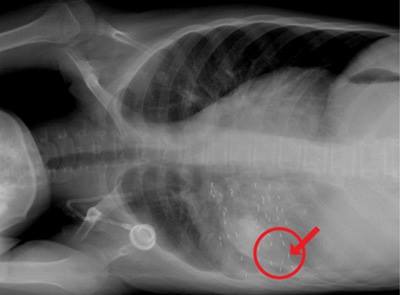

ผลก็คือมีคนไทยไปรักษามะเร็งที่นั่นจำนวนไม่น้อย วิธีที่แปลกแหวกแนวนอกเหนือข้อกำหนดทางการแพทย์สากลว่าด้วยการรักษามะเร็งก็คือ การฝังแร่ถาวรเข้าไปล้อมก้อนมะเร็งในร่างกาย วิธีนี้การแพทย์แบบแผนมีใช้เหมือนกัน เฉพาะกับมะเร็งต่อมลูกหมากในระยะต้น แต่รพ.แห่งนี้เล่นใช้วิธีนี้กับมะเร็งทุกมะเร็ง ทุกระยะ เช่น มะเร็งเต้านม มะเร็งปอด กระทั่งมะเร็งที่แพร่กระจายไปปอด กระดูก ท้อง สมอง ก็ฝังเข้าไปตามอวัยวะนั้น ๆ จากนั้นก็ให้ผู้ป่วยกลับบ้าน แล้วนัดไปฝังแร่ซ้ำอีกหลาย ๆ ครั้งจนผู้ป่วยบางรายก็เสียชีวิต

การปล่อยให้ผู้ป่วยกลับบ้านไปเลยทั้งที่มีแร่กัมมันตภาพรังสีอยู่ในตัว และแพร่รังสีไปรอบทิศ ผู้คนรอบข้างที่รับรังสี ถ้าเป็นหญิงมีครรภ์มีสิทธิ์ทารกตายคลอด คลอดผิดปกติ พิกลรูป ทั้งเด็กเล็ก และผู้ใหญ่อาจเป็นมะเร็งได้อีกด้วย

ที่ศิริราชพบว่ามีผู้ป่วยหลายรายมีปริมาณรังสีแพร่กระจายออกมาทางผิวหนังมาก ศัลยแพทย์ พยาบาล และเจ้าหน้าที่ระดับต่าง ๆ ที่เข้าไปดูแลรักษาผู้ป่วยต้องโดนรังสี รวมทั้งคนในครอบครัว ญาติพี่น้องและเพื่อนฝูงในที่ทำงานอีกด้วย

แม้เมื่อผู้ป่วยตายไป กัมมันตภาพรังสีก็ยังอยู่ในศพ กระทั่งเถ้ากระดูก